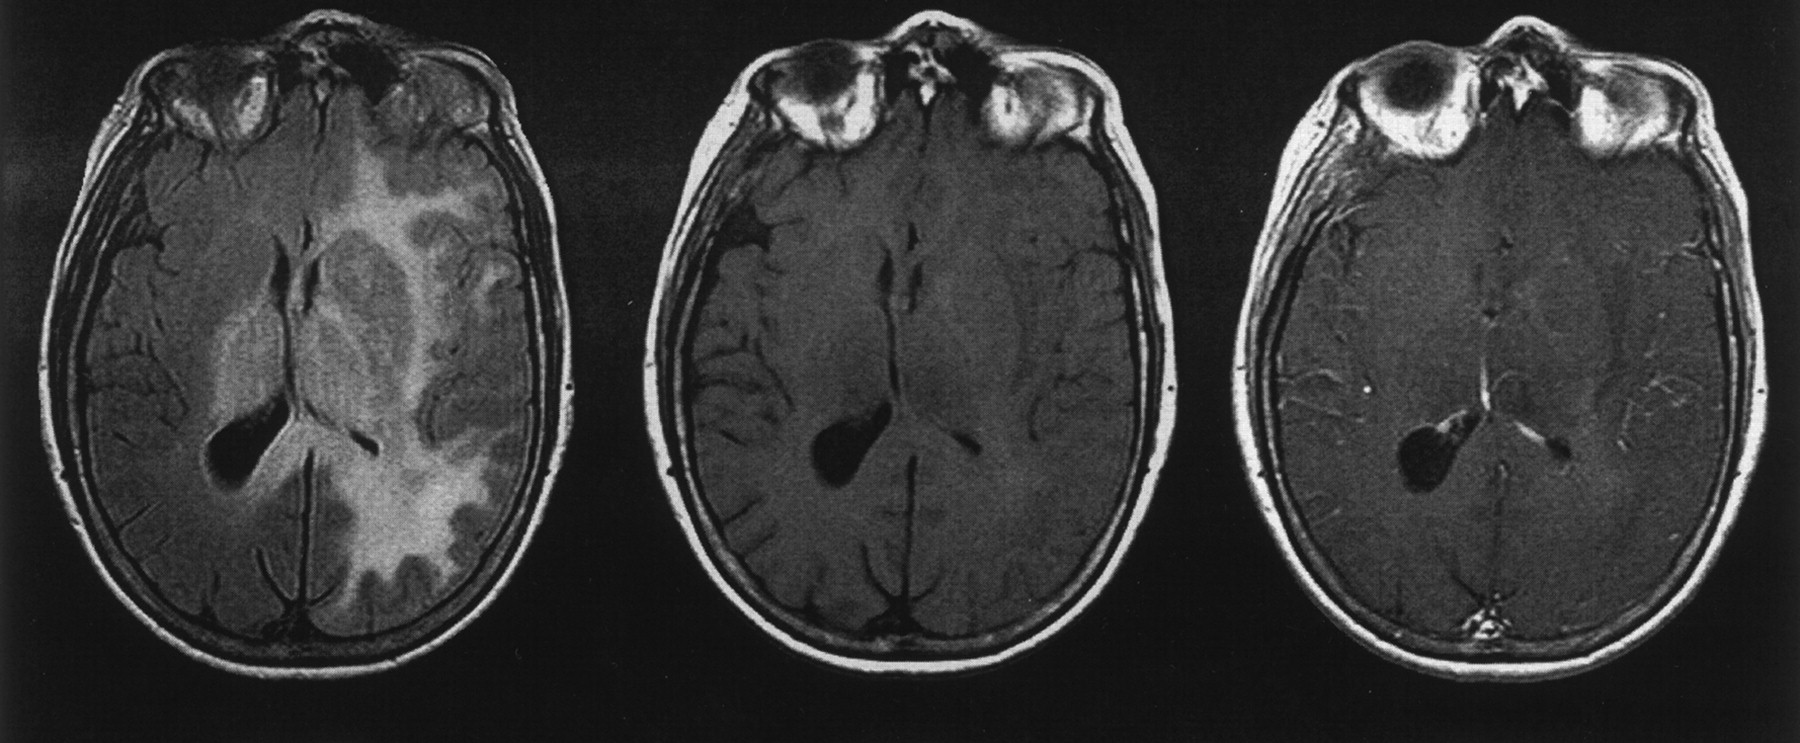

CT of the brain revealed mild left hemispheric mass effect. MR imaging and proton MR spectroscopy were performed on a clinical whole body 1.5-T imaging unit. T2-weighted fast spin-echo (3555/96/1 [TR/effective TE/number of excitations]) and fast FLAIR (7155/112/1; inversion time, 2000 ms) images revealed diffuse hyperintensity involving the left cerebral white matter and basal ganglia, bilateral thalami, and splenium of corpus callosum. Relatively mild mass effect was observed on the left lateral ventricle, and no appreciable enhancement or evidence of necrosis was seen on the T1-weighted images (Fig 1).

Spin-echo MR images. Axial view FLAIR image (left) shows extensive hyperintensity involving the left hemisphere white matter and basal ganglia, bilateral thalami, and splenium of corpus callosum, with mild mass effect. Comparison between unenhanced T1-weighted image (center) and contrast-enhanced T1-weighted image (right) reveals no appreciable enhancement.